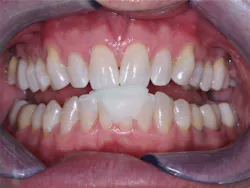

Dental sleep medicine is growing rapidly. Why? A large portion of the adult population in the US has an objectionable snoring problem. Do they want to quit snoring? Of course! Although most physicians place their snoring patients on a CPAP device, many patients are not compliant. Is there another way to stop snoring? Absolutely. You can do so with a well-made snoring appliance (figures 1 and 2).